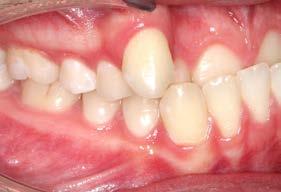

Figura 3. Lateral derecha. Figura 4. Izquierda de inicio. Figura 5. Frente. Figura 6. Overjet, laterales derecha e izquierda.

Las fotografías intraorales muestran las relaciones molares clase II y las relaciones caninas clase II bilaterales (Figura 3 y 4), espaciamiento anterosuperior, un overjet y overbite aumentado (Figura 5). La forma de los arcos es cuadrada, superior e inferior, con el apiñamiento moderado inferior y los espacios en superior.